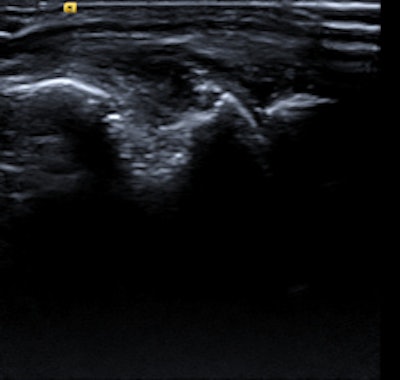

Elderly patient with established and treated rheumatoid arthritis. The patient complained of increased pain and stiffness. Ultrasound shows active synovitis and erosions in multiple metacarpo-phalangeal joints (a = grayscale image, b = power Doppler image). Ultrasound is a useful tool to assess for the presence and to an extent severity of (subclinical) inflammation. Clinical examination can be surprisingly insensitive even in florid inflammation, as shown here. Images courtesy of Dr. Bernhard Tins.Imaging in rheumatology was in the past largely confined to radiographs of the hands and sacroiliac joints helping to establish the diagnosis and then monitoring disease progression. Because radiographs are not very sensitive for early inflammation in inflammatory rheumatic disorders, the demand on imaging services was therefore limited, Tins and Butler explained. Over the last 10-15 years, new drugs and new technologies have brought fresh challenges and opportunities to rheumatology and radiology. New drug treatments allow more effective treatment, preventing many complications, and early diagnosis and disease monitoring have become the major challenges.